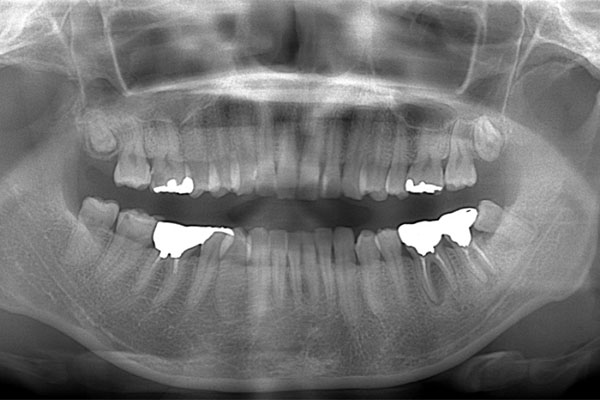

患者様の初診時レントゲン写真

【担当医師所見】

咬合平面の整頓の必要性 有

交叉咬合、オーバージェットの是正

歯周病の治療の必要性

ブラッシング方法の教授